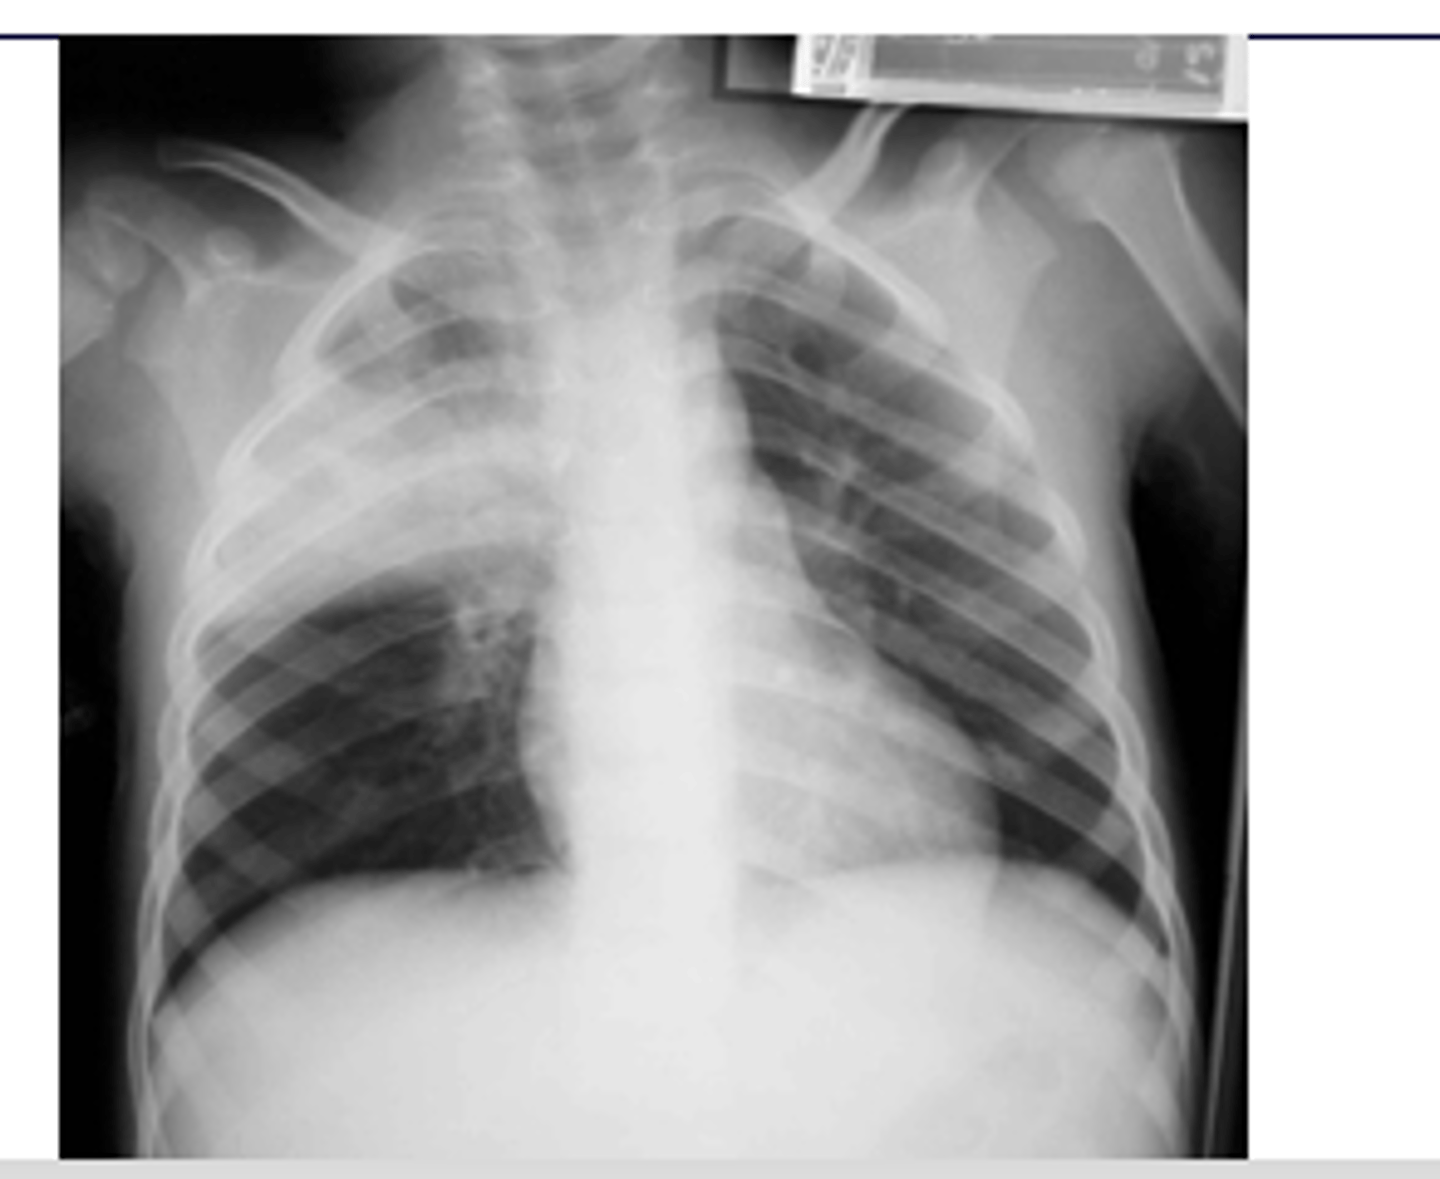

ID picture on back

RUL pneumonia with air bronchogram sign

<p>RUL pneumonia with air bronchogram sign</p>